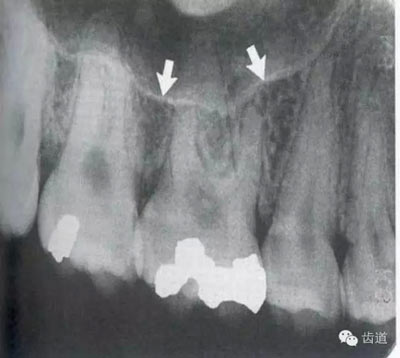

是介于牙槽窩和牙骨質(zhì)之間的結(jié)締組織。牙周膜的厚度一般在0.15~0.38mm之間。X線上顯示為包繞牙根連續(xù)不斷的密度低的線條狀影像,其寬度均勻一致

即固有牙槽骨,是牙槽骨的內(nèi)壁,圍繞牙根,骨質(zhì)致密而薄,X線片上顯示為包繞牙根的連續(xù)不斷的密度高的線條狀影像。